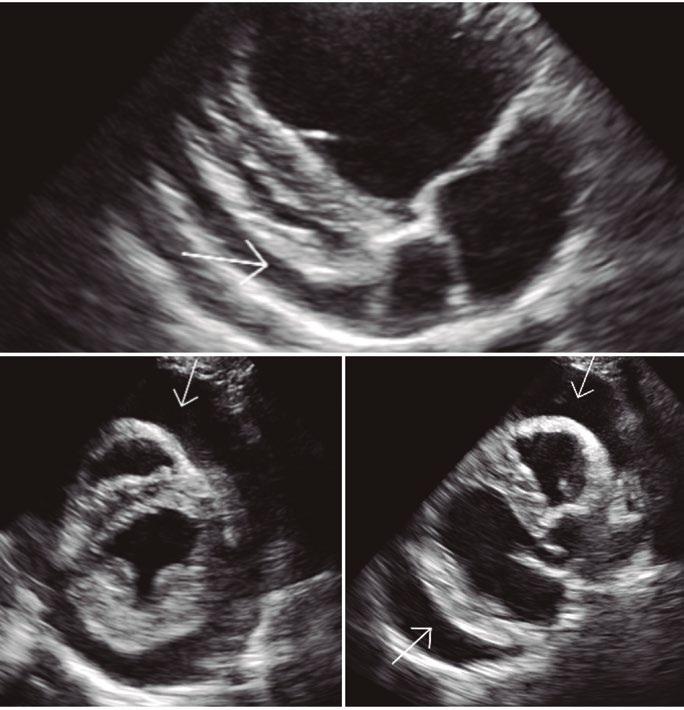

Utilidad clínica de la ecografía pulmonar y cardiaca en urgencias